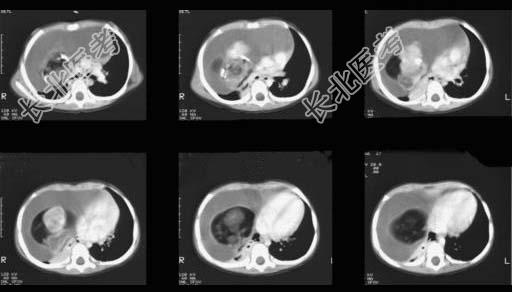

- 单项选择题12岁,女, 咳嗽、咯血1个月,咳出毛发、钙化物, 请结合图片,选择最可能的诊断 ( )

D、畸胎瘤